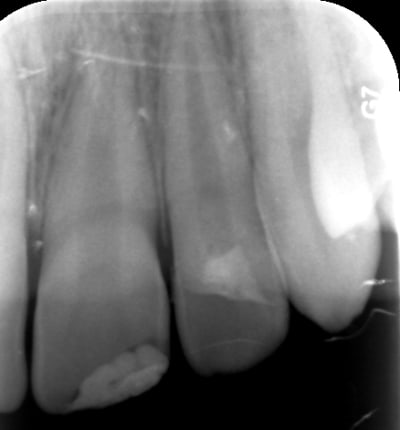

6 mois plus tard : tout va bien pour la 12 mais la 11 est nécrosée. L'apex étant large (60), j'ai placé un bouchon de MTA.

A revoir dans 6 mois...